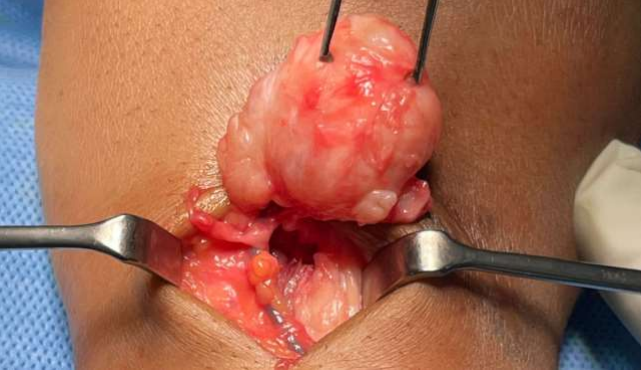

To obtain a definitive diagnosis, an excisional biopsy was performed under general anesthe-sia, revealing a 3x3 cm non cystic hard soft tissue mass attached to the dorsal joint capsule. The lesion was well circumscribed, and the encapsulated lesion was completely excisiond. The adjacent tendons and vessels were taken care of to avoid damage.

Figures 1,2,3,4,5,6

Figure 1